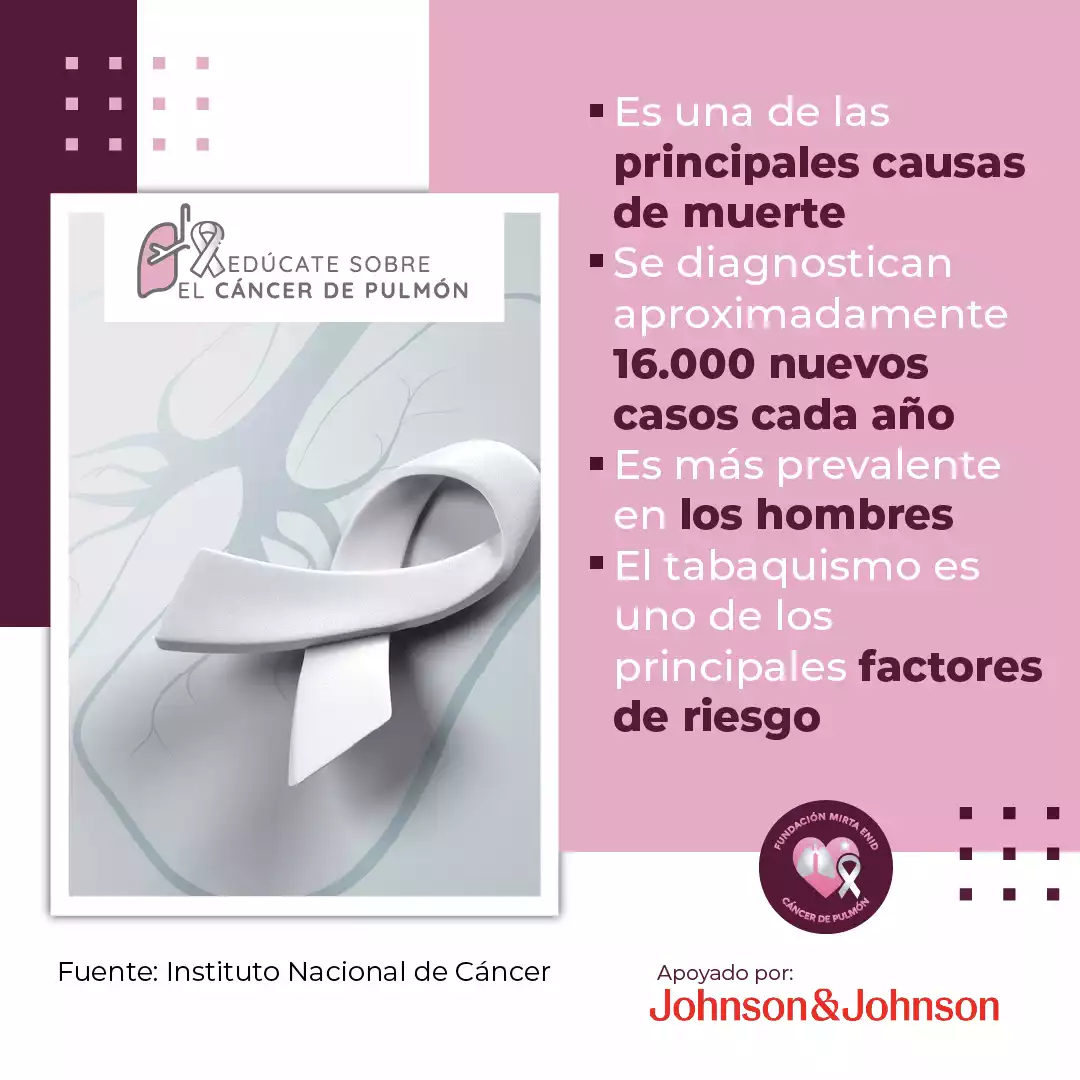

Esta iniciativa busca generar mayor conciencia sobre uno de los cánceres más prevalentes en Puerto Rico, que ocupa el tercer lugar entre los más diagnosticados en hombres y mujeres, y es la segunda causa principal de muerte por cáncer, según la Asociación Puertorriqueña del Pulmón.